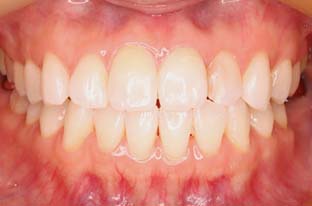

セラミッククラウン

の症例

| 主訴 | 前歯の形や大きさが気になる。 以前にかぶせ物を入れたが、 自分の顔に合っていない気がする。 |

| 年齢・性別 | 30代・女性 |

| 治療期間 | 2ヶ月 |

| リスク・副作用 | 噛む力が強い方の場合、セラミックが欠けてしまうことがあるので、就寝時にマウスピースを装着していただく必要があります。 |

| 治療内容 | ジルコニアボンドクラウンを用いて、 強度も審美も最高のもので、 歯茎の高さも合わせて完成させる。 |

| 治療費用 | 5,500円(税込)×4 (プロビジョナルレストレーション(仮歯)×4本) 歯ぐきの手術 55,000円(税込) |

| 治療方針 | 左右の歯のバランスを同じ数値で シンメトリーとする。 |

| 特記事項 | 回数かかっても良いので、 キレイに美しく仕上げて欲しい。 |